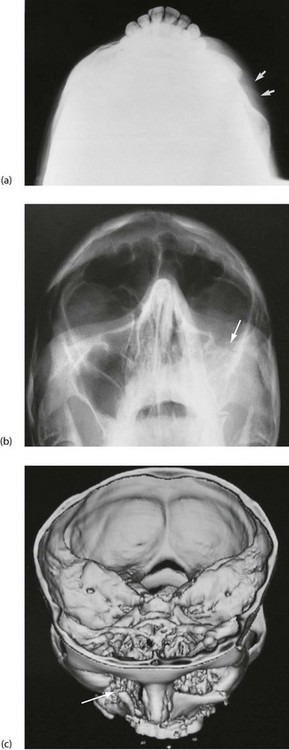

Fig. 16.11 Depressed zygomatic fractures

(a) Submento-vertical projection of a 43-year-old man who had been punched on the left cheek showing a depressed fracture of the zygomatic arch (arrowed). (b) 30° Occipito-mental radiograph after a similar injury in a different patient. This patient had a depressed ‘tripod’ fracture of the zygoma manifest by discontinuity of the lower orbital margin (arrowed). Note that since the roof of the maxilla is involved, the maxillary sinus (the antrum) has typically filled with blood and is rendered radiopaque. (c) 3D reconstruction of CT scans showing a severely depressed fracture of right lower orbital rim involving maxilla and zygomatic body (arrowed). The left lower orbital rim is also fractured and displaced